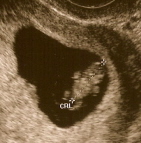

This was my 8 week 2 days sono:

|